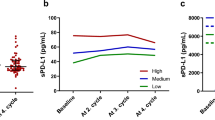

Perioperative changes in sPD-L1 levels in peripheral blood

Preoperative plasma sPD-L1 levels were suggested not to be associated with tcPD-L1 expression. In this context, to rule out the possibility that only PD-L1-expressing tumor cells contributed to sPD-L1 levels in peripheral blood, we examined postoperative plasma sPD-L1 levels in patients who underwent radical surgery including lobectomy or segmentectomy and lymph node dissection (n = 61) (Supplementary Table 1). The median preoperative serum sPD-L1 level was 63.4 pg/mL, and 1 month after surgery, the median sPD-L1 level (n = 55) had significantly increased to 72.2 pg/mL (P < 0.001) (Fig. 2). Furthermore, at 3 months after surgery, the median serum sPD-L1 level (n = 51) had significantly decreased to the preoperative level (62.0 pg/mL, P = 0.019) (Fig. 2). These data demonstrated that despite completely removing tumor cells, plasma sPD-L1 levels were temporarily increased and then subsequently recovered to the initial levels, suggesting that some factor(s) other than tumor cells, such as an inflammatory immune response, might contribute to sPD-L1 levels in peripheral blood.

Changes in plasma soluble PD-L1 (sPD-L1) levels in plasma during the perioperative period in patients who underwent radical surgery, including lobectomy and dissection of regional lymph nodes, for non-small cell lung cancer. Plasma sPD-L1 levels were measured by ELISA before surgery (n = 56), 1 month (n = 53), and 3 months (n = 50) after surgery. The data from patients with benign pulmonary tumor are plotted (n = 6). Red bars indicate the median sPD-L1 levels in plasma